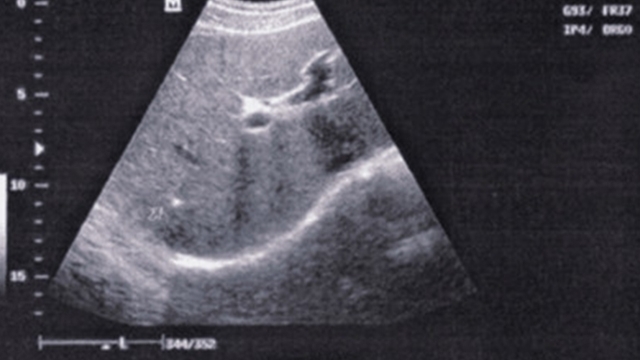

我先让他坐下,慢慢说。据刘贤军(化名)自述,感染乙肝已经20多年了,当时查出来是乙肝大三阳,当时条件不好,也没有引起足够的重视。最近感觉身体干啥都提不起劲儿,吃啥都没胃口,就担心是自己的健康出现了问题,希望李主任能够帮帮我。当我看到他的B超检查单的时候,结果显示,早期肝硬化。我在想,这肯定是他这些年放松了对身体健康的重视,才导致的乙肝引起的早期肝硬化。